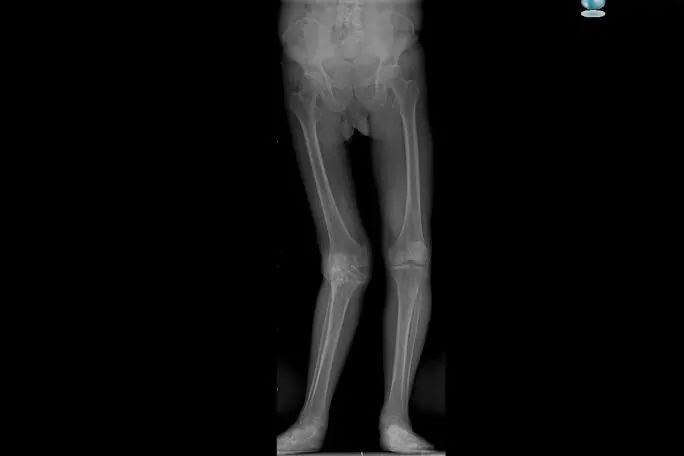

58岁的尤大叔是晋江内坑人,9年前因外伤导致右侧胫骨近端骨折,在外院进行手术治疗。但术后恢复欠佳,尤大叔行走状况逐渐受限,右膝关节严重外翻,因经济原因一直未进行系统治疗,生活、工作上带来的不便让他苦不堪言。

▲术前影像

11月10日,受益于“我为群众办实事”实践活动——“晋江市髋膝关节置换救助工程”项目,尤大叔入院进行手术治疗??悸堑交颊呦ス亟谘现夭晃榷?、韧带功能丧失,上海市第六人民医院骨科副主任、主任医师,上海六院福建医院副院长沈灏教授选择了旋转铰链膝对患者行全膝关节置换术。